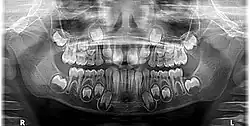

Radiografia panorâmica - nessa imagem pode ser observada a fase de dentição mista, com dentes permanentes e decíduos presentes.